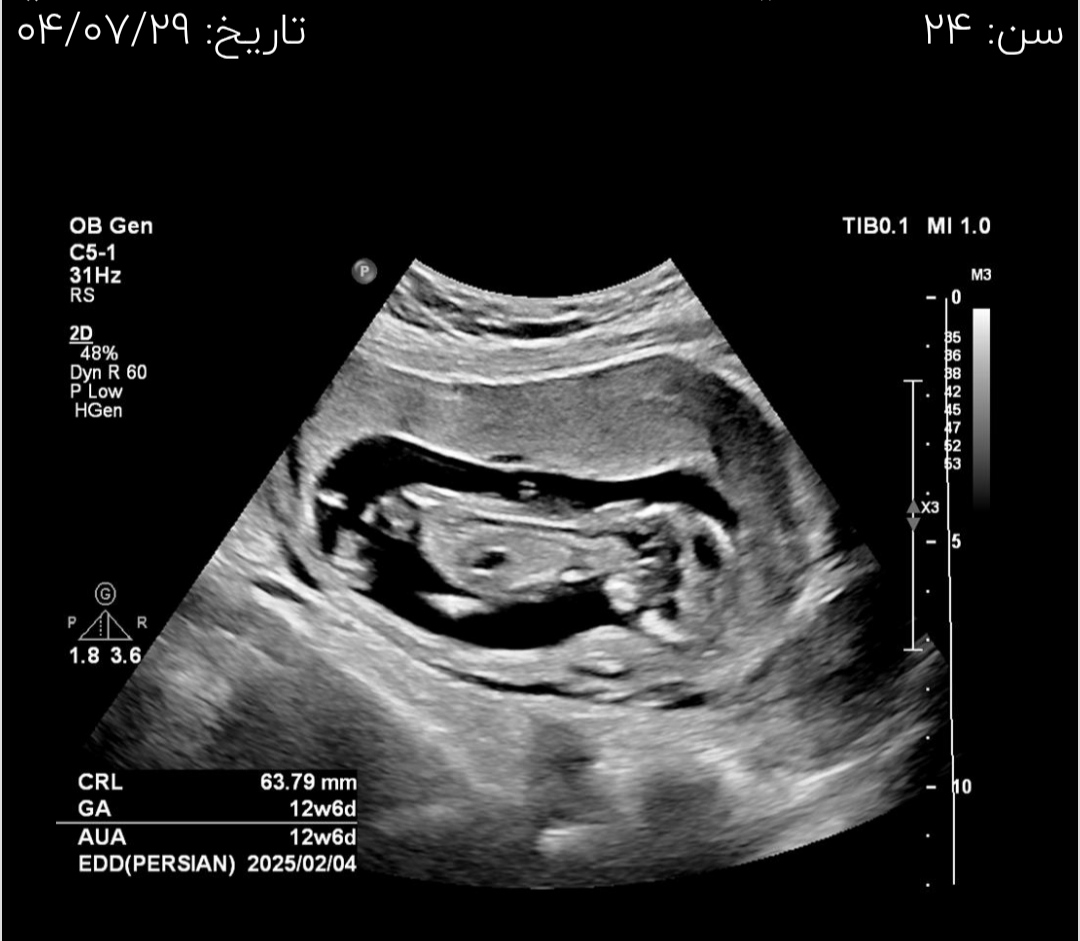

اینم عکسا بچه

عزیزم متن آخر برای همه هست یک نوع متن هشداری است که تنها راه تشخیص قطعی مشکلات ژنتیکی آمنیوسنتز است، یعنی برای شخص شما نیست، برای تمام مادران ما این را میگوییم که غربالگری تعیین درصد خطر هست تشخیص نهایی با آمنیوسنتز هست یک گزاره خبری است مثل این که در تلویزیون بگویند هوا برفی است، اگر میخواهید تصادف نکنید زنجیر چرخ لازم است آیا خطاب با شما است؟ نه اطلاعیه ای برای همه مردم هست همین و بس

درمورد nb در طی سال های اخیر کلا در سیستم نوین گزارش دهی nb از سونوگرافی سه ماهه اول حذف شده در آنومالی گزارش میگردد و برای همین گفته اند nb را وارد گزارش نکنید